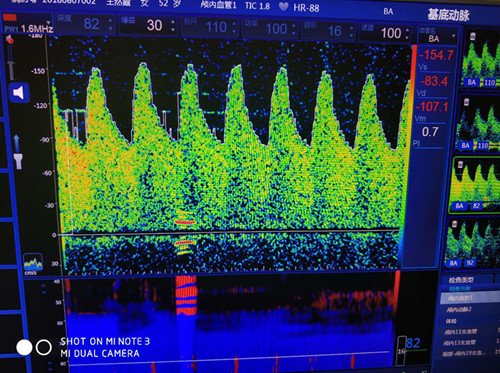

近日,一名中年女性在我院功能科進(jìn)行經(jīng)顱多普勒(TCD)體檢時(shí),主檢醫(yī)師發(fā)現(xiàn)該女性后循環(huán)動(dòng)脈血流速度異常增高,前循環(huán)動(dòng)脈呈相對(duì)低波動(dòng)改變,雙側(cè)壓頸試驗(yàn)陰性。這種異常的顱內(nèi)動(dòng)脈改變引起了主檢醫(yī)師的關(guān)注,遂請(qǐng)科里高年資醫(yī)師進(jìn)行進(jìn)一步詳細(xì)檢查。經(jīng)過(guò)詢問(wèn)病史,并結(jié)合TCD檢查結(jié)果和頸動(dòng)脈超聲觀察,最終診斷為煙霧病。

基底動(dòng)脈血流速度增高